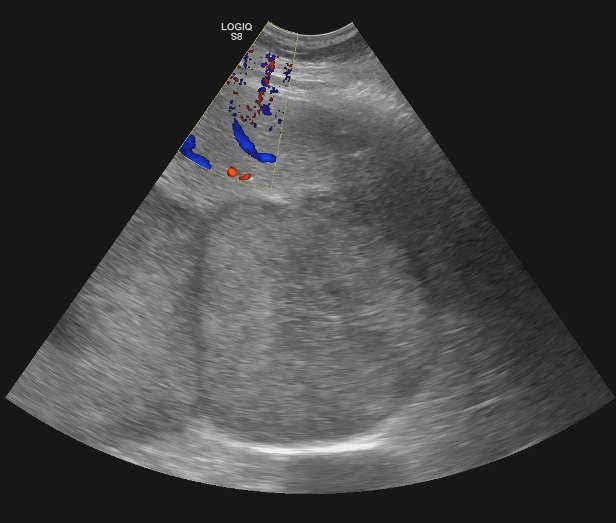

Descripción de los hallazgos ecográficos y las imágenes más relevantes para la resolución del caso

Se realiza ecografía abdominal en la consulta que muestra abundantes lesiones ocupantes de espacio en ambos lóbulos hepáticos, alguna de gran tamaño.Otras pruebas complementarias realizadas (si existen)